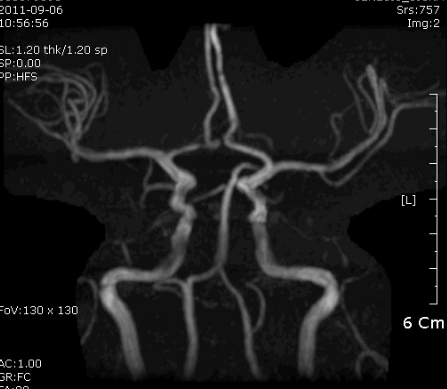

사진에는  left PCA distal 이후가 보이지 않습니다. (맞나요..?)

일단 pca 영역에 A to a or cardioembolism 생각할 수 있습니다.

Anterior choroidal과 posterior choroidal artery의 영역을 공유하는 경우가 있는 것 같습니다. anterior choroidal 막히면 poster choroidal artery 가 대신 혈액공급을 담당하는 경우가 있습 것 같습니다.

두 혈관은 서로 collateral 있습니다. 그러므로 한쪽이 hypoplasia나 chronic stenosis 있다면 PChA가  AChA 영역을 보충할 수 있는 것 같습니다. (Sohn's theory).  이환자에서 anterior choroidal artery가 서서히 막혀서 posterior choroidal artery가 대신 그 역활을 하고 있는데  left PCA 영역에  A to A가 생겼다면 가능......

아니면 이 환자가 두가지 병변으로 나누어 동시다발적으로 생겼을 가능성...

따라서 borderzone 은 아니고, PCA 영역의 artery to artery embolic stroke 일 가능성이 높다고 생각함.